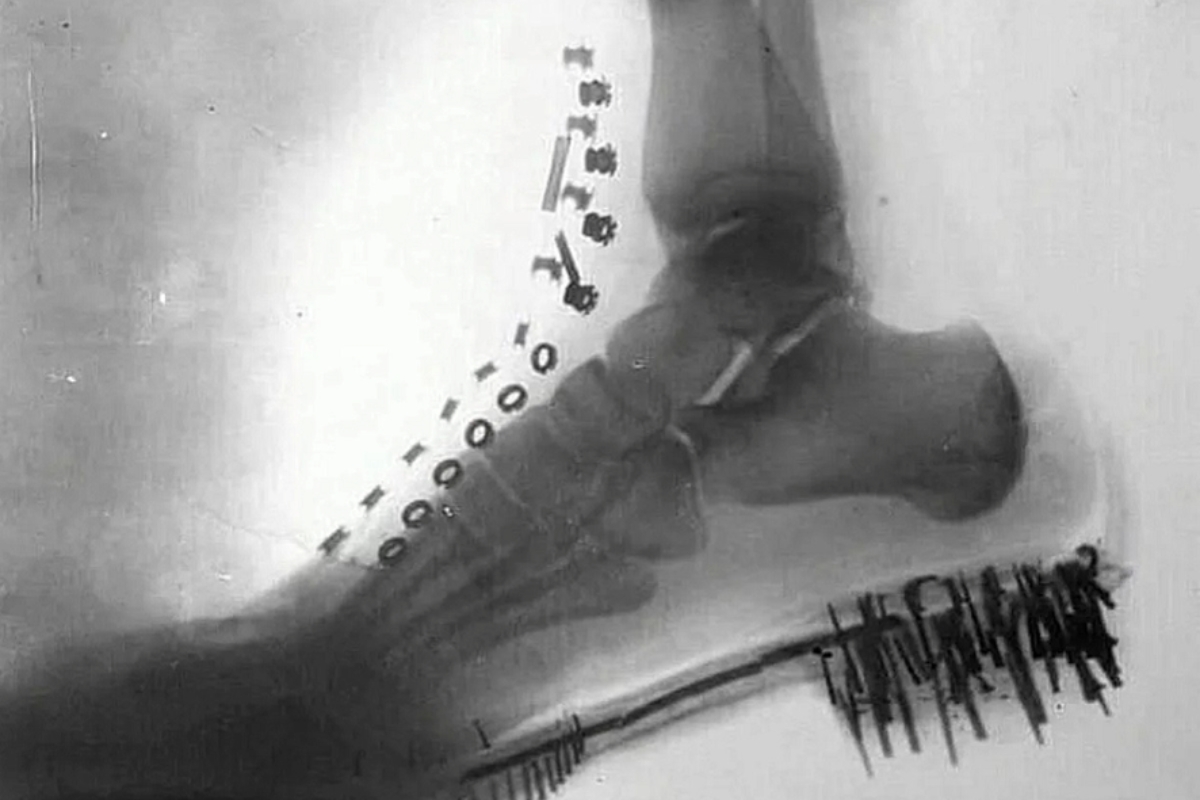

Nikola Tesla did something that still impresses when the subject is technology and science. In 1896, he was already producing radiographic images of his own foot and hand, just a few months after the official announcement of the discovery of X-rays by Wilhelm Conrad Röntgen in November 1895.

Tesla used high-voltage coils and vacuum discharge tubes developed by him to generate the images. The result was the production of radiographs of his own foot and hand still in 1896.

While the term X-ray was quickly becoming popular in the international press between 1896 and 1897, Tesla preferred to call these images shadowgraphs, reinforcing a vocabulary of his own for a phenomenon that was still being understood.